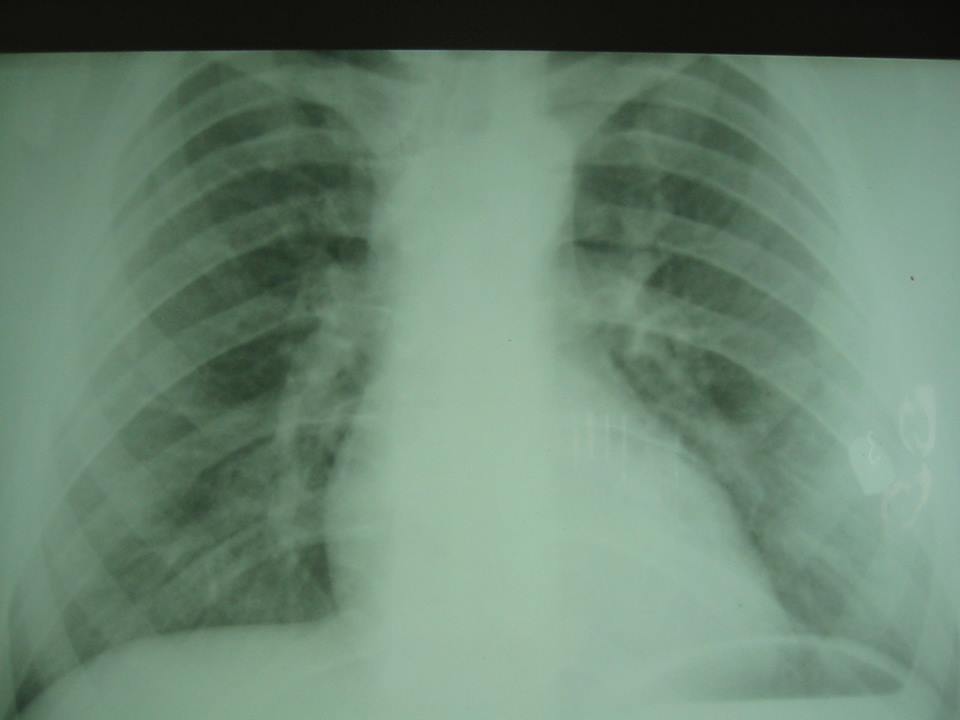

Ky operacion ka të bëjë me heqjen e plumbit nga kraharori, plumb i cili gjendej afër zemrës së një 20 vjeçari.

Doktor Salih Krasniqi, përmes një postimi në facebook i ka treguar edhe fotografitë se si është realizuar operacioni.

Por ky operacion, është bërë pa u prerë fare kraharori dhe ka zgjatur vetëm 19 minuta.